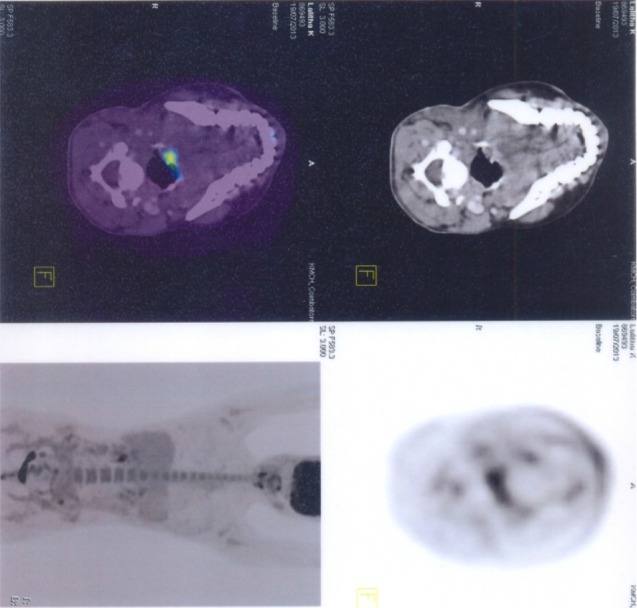

Wound healing was uneventful. Patient was apparently normal without any complaints at the time of discharge. Later she complained of hoarseness of voice and cough reflex while taking solid food. An ENT opinion was obtained. Endoscopic examination revealed right vocal cord palsy. She was advised certain exercises and told to consume food in head elevated position to avoid aspiration. Patient is being followed up for past one and half years and she is free of aspiration and coughing except for mild hoarseness of voice. One month after surgery a whole body PET scan was performed. It gave an impression of no definite evidence of metabolically active disease anywhere in the whole body. Two months after surgery patient had her menstrual cycle. A 24 h urine metanephrine test was done to rule out active paraganglomas in other sites and the results where negative.

Fig. 6.

Pet scan shows no evidence of metabolically active disease in whole body